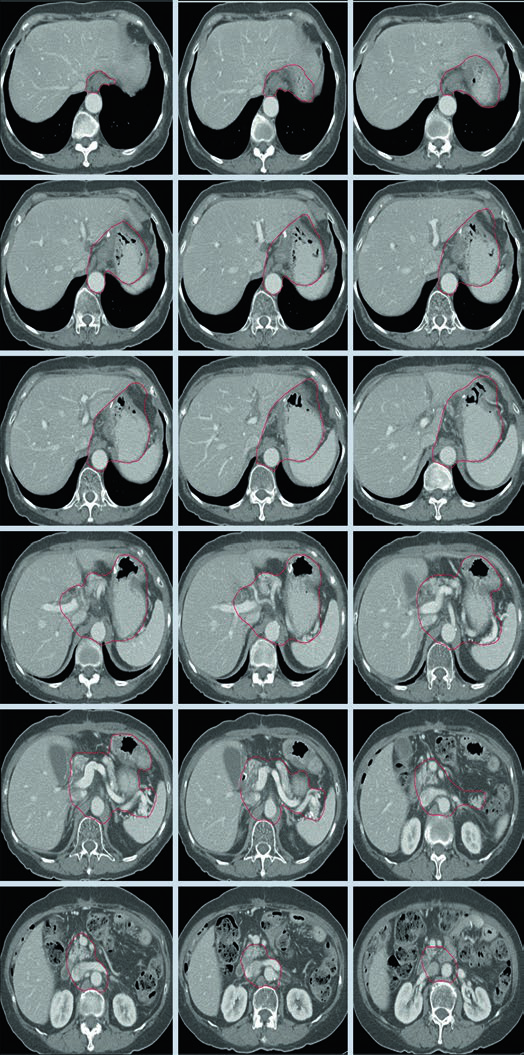

Caso 2: T3N3M0 Adenocarcinoma do Corpo — Gastrectomia Distal

Com doença T3N3, o CTV é extenso: inclui anastomose gastrojejunal, estômago remanescente, artéria celíaca, hilo esplênico e leito tumoral pancreático. Esse cenário exige atenção especial às restrições de dose nos órgãos de risco — particularmente rins e fígado — pois o volume de tratamento é considerável.